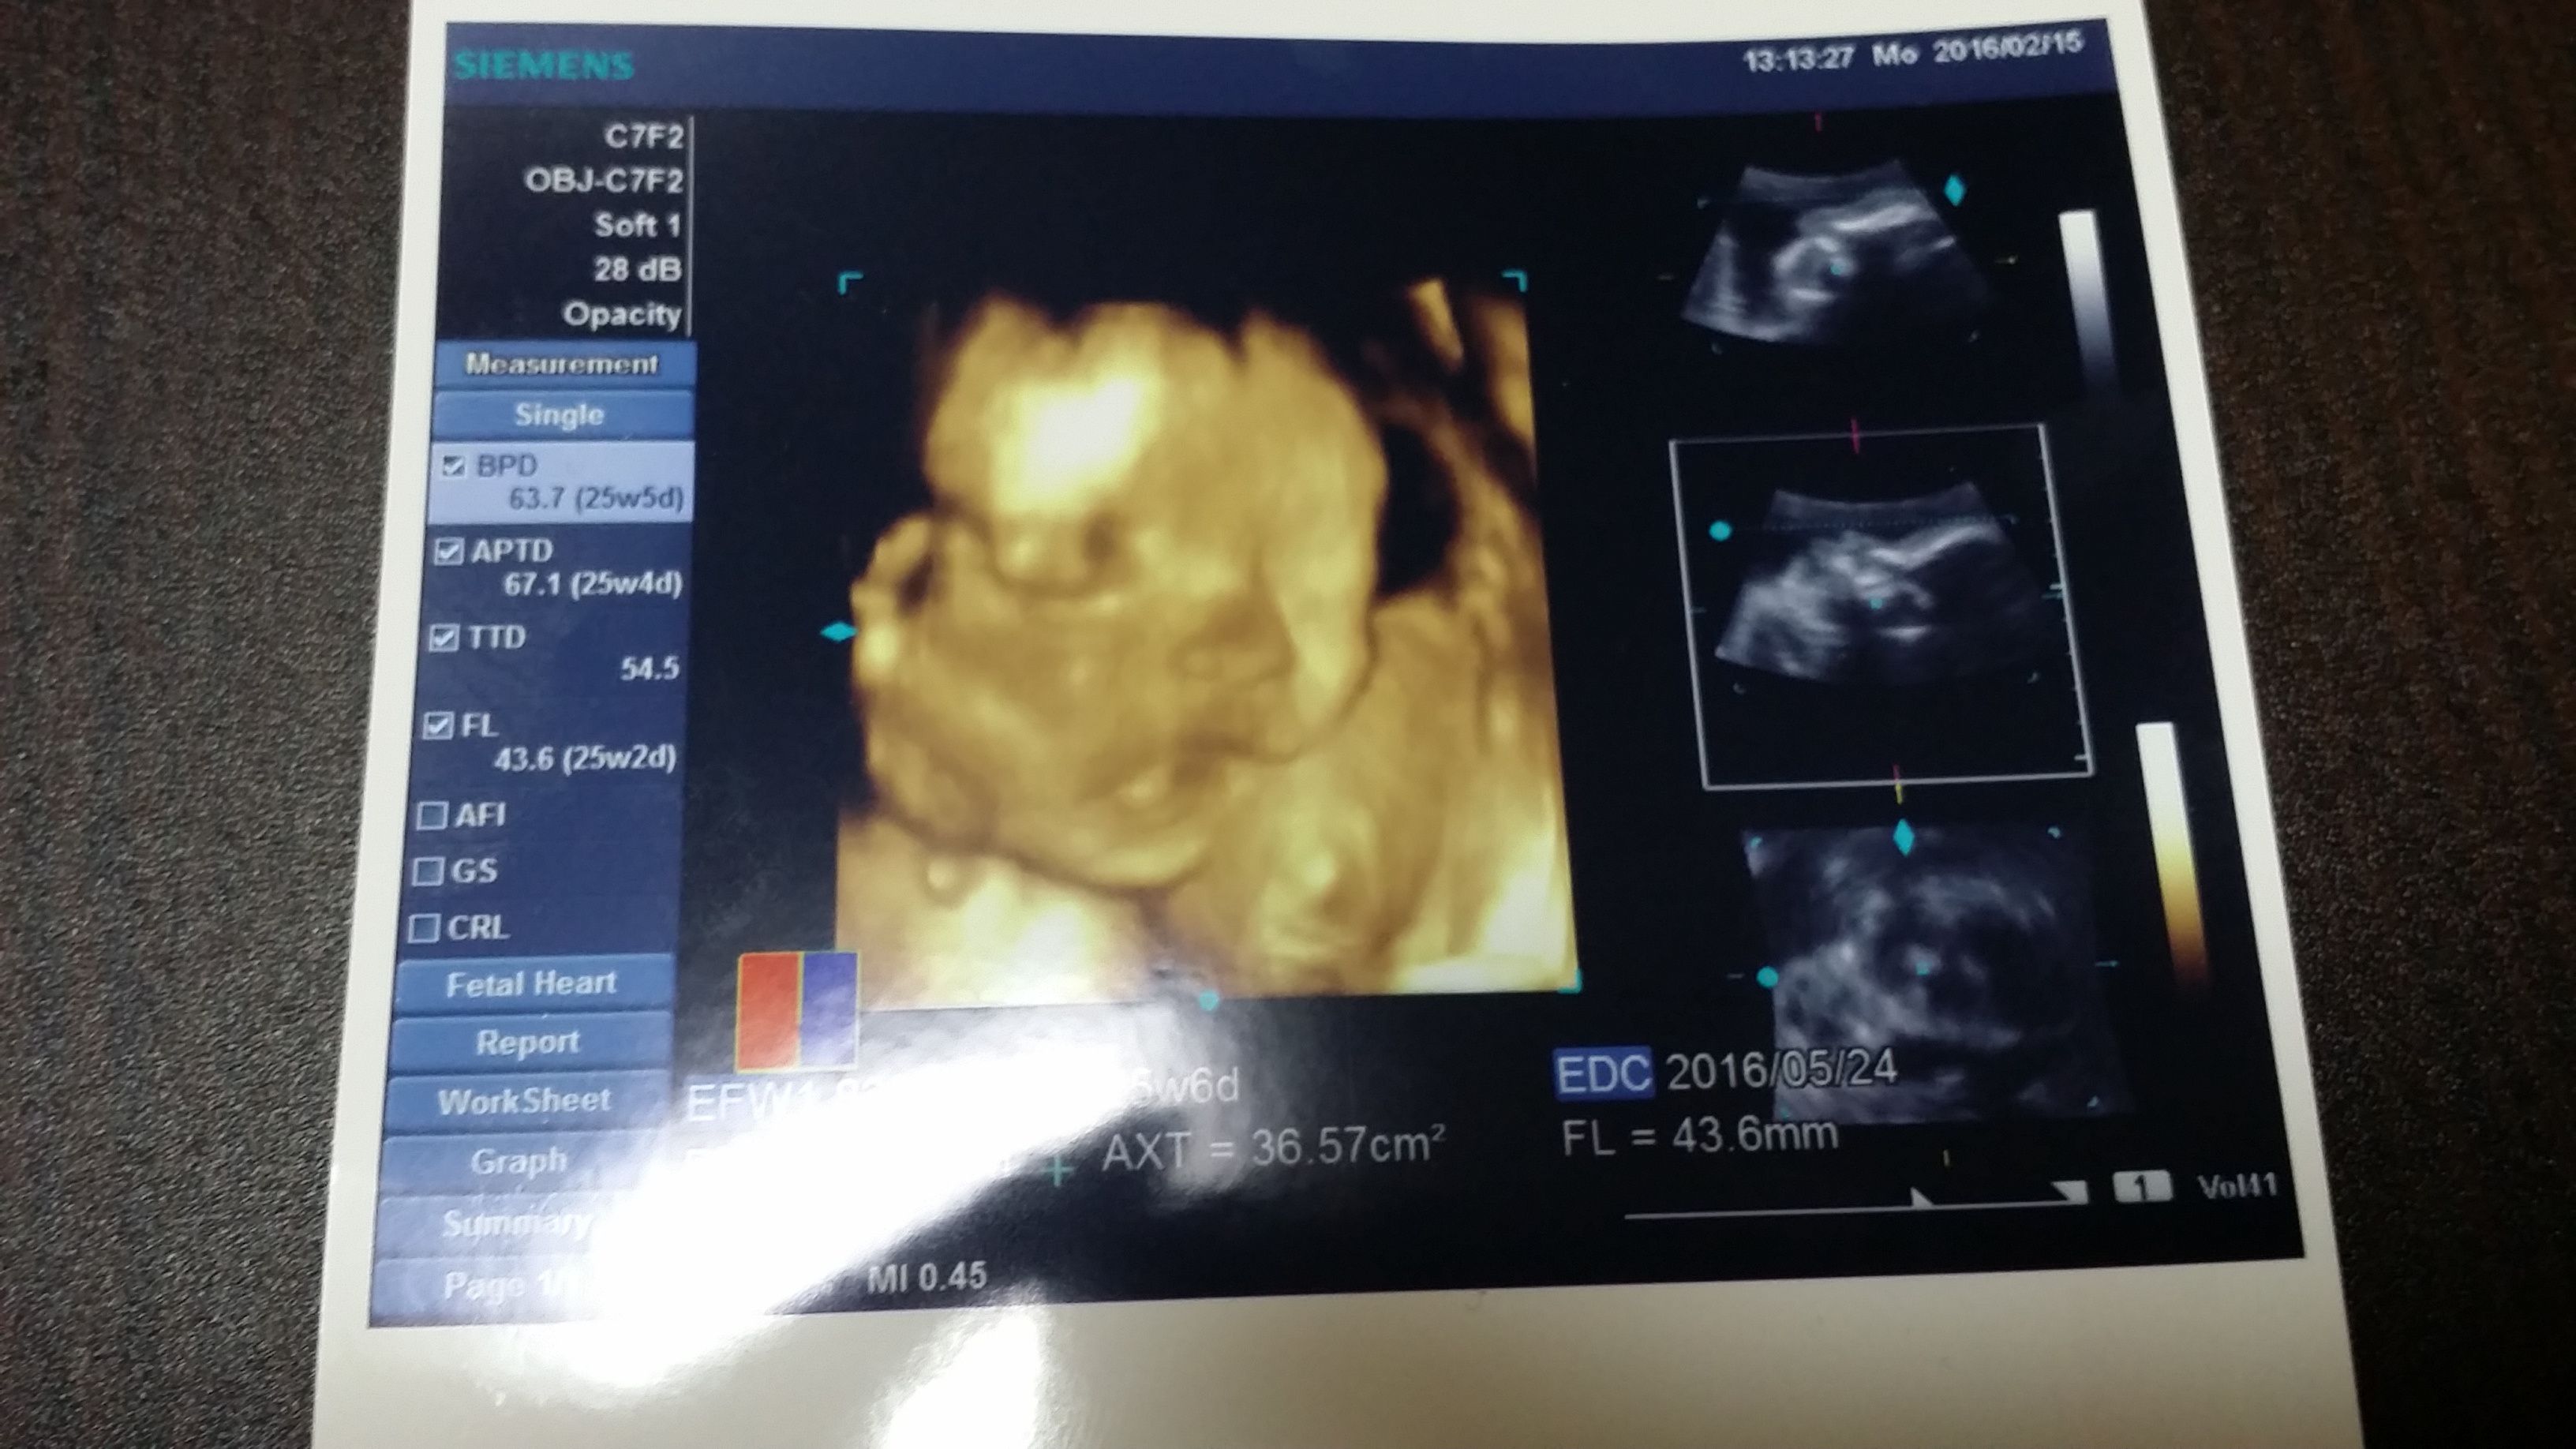

今日の検診で赤ちゃんは「男の子」だと分かりました!

2016-02-15 21.01.36.jpg